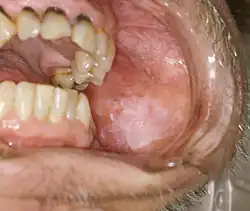

Proliferative verrucous leukoplakia

Proliferative verrucous leukoplakia (PVL) is a recognized high risk subtype of non-homogeneous leukoplakia.[19] It is uncommon, and usually involves the buccal mucosa and the gingiva (the gums).[20] This condition is characterized by (usually) extensive, papillary or verrucoid keratotic plaques that tends to slowly enlarge into adjacent mucosal sites.[1][2] An established PVL lesion is usually thick and exophytic (prominent), but initially it may be flat.[20] Smoking does not seem to be as strongly related as it is to leukoplakia generally, and another dissimilarity is the preponderance for women over 50.[20] There is a very high risk of dysplasia, transformation to squamous cell carcinoma with high mortality (PVL does not transform into verrucous carcinoma, which is a lesion with a good prognosis usually; the similarity of names does not reflect the common origin, but only the resemblance of their appearance).[2][21]